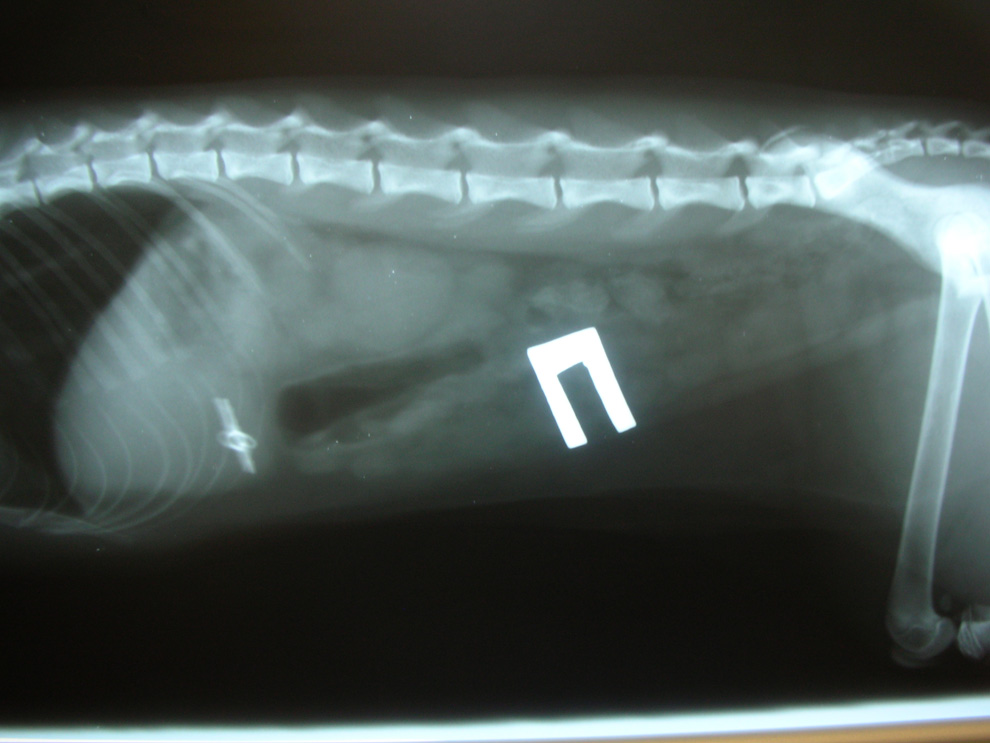

Диагностика в ветеринарной клинике

При посещении клиники ветеринар сначала осматривает собаку. Сразу обнаружить инородное тело можно, если оно застряло в глотке. Если проглочен крупный и твердый предмет, его можно нащупать при пальпации брюшной полости. В остальных случаях применяется инструментальная диагностика.

- Рентгенография поможет выявить наличие металлических, резиновых предметов, камней. На рентгене также видна деформация и другие изменения в органах пищеварительного тракта, характерные для присутствия инородного тела.

- Чтобы точно определить место предмета и проследить его продвижение по пищеварительному тракту, делается рентген с контрастным веществом. Чаще используется барий.

- Ультразвуковое исследование поможет определить наличие любого инородного тела. На УЗИ видно, если кишечник закупорен.

- Эндоскопия – самый информативный метод обследования. Он подтвердит наличие постороннего предмета в пищеварительном тракте и поможет оценить состояние слизистой.